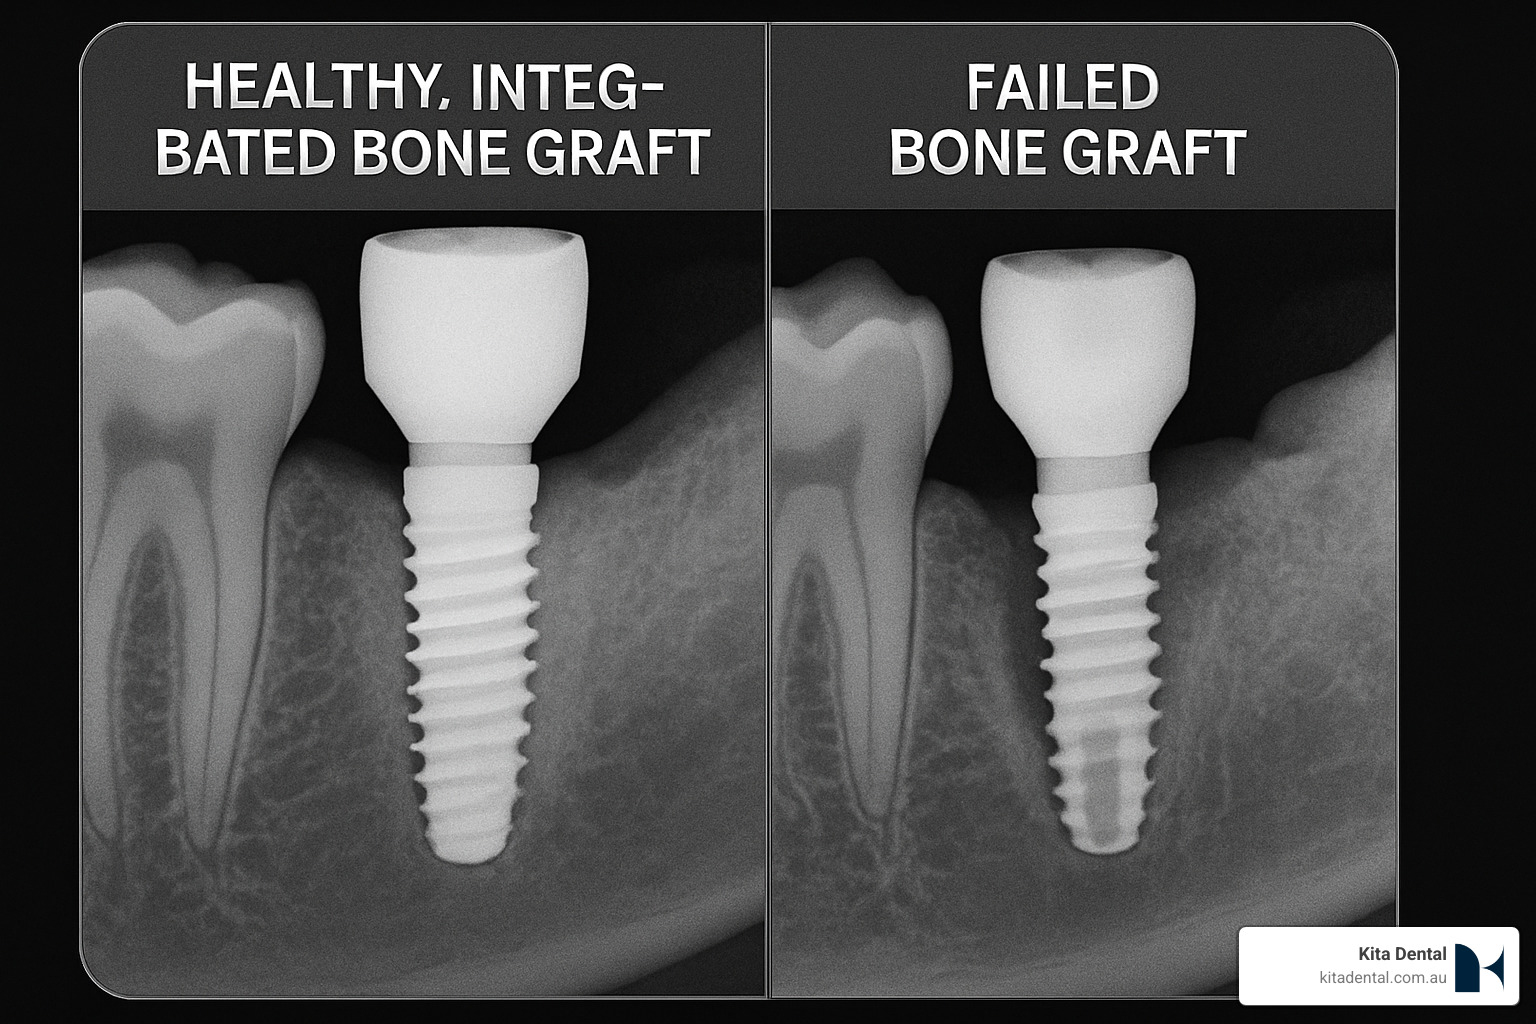

This is where osseointegration becomes crucial. This process describes how your jawbone actually fuses with a titanium implant, creating a rock-solid foundation that can handle the incredible forces of chewing. For this process to work properly, we need healthy bone surrounding the entire implant.

When dental implants are placed into properly healed bone grafts, they achieve 95-98% success rates even after 10+ years.

Recognizing Potential Problems Early

Infection is the most common concern but is usually easily treated when caught early. Warning signs include pain that gets worse after day 3 or 4, pus or unusual discharge, fever above 38°C, or persistent foul taste.

Graft failure is rare but can occur, especially in smokers. Signs include graft particles that remain loose weeks after surgery or lack of bone formation on follow-up X-rays.

What are warning signs of graft failure?

While graft failure is uncommon, knowing what to watch for helps us catch problems early when they’re easiest to treat.

Pain that doesn’t follow the expected pattern is worth investigating. Normal discomfort should gradually improve after the first few days. If your pain increases after the first week or becomes severe and throbbing, contact us.

Signs of infection require immediate attention. Watch for pus or unusual discharge, fever above 38°C, or persistent foul taste that doesn’t improve with gentle rinsing.

Healing problems like visible graft material through your gums after initial healing, or unusual swelling that increases rather than decreases over time also warrant examination.

Most complications are easily treatable when caught early. We maintain open communication throughout your healing period.